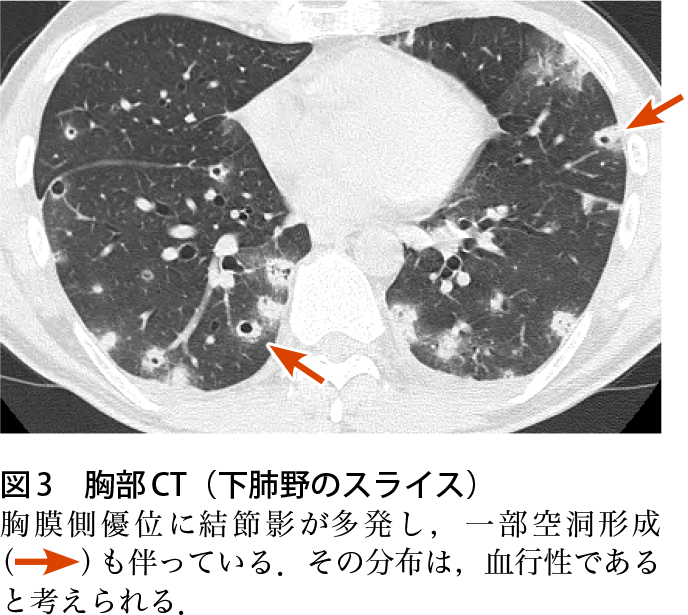

症例4 診断と解説